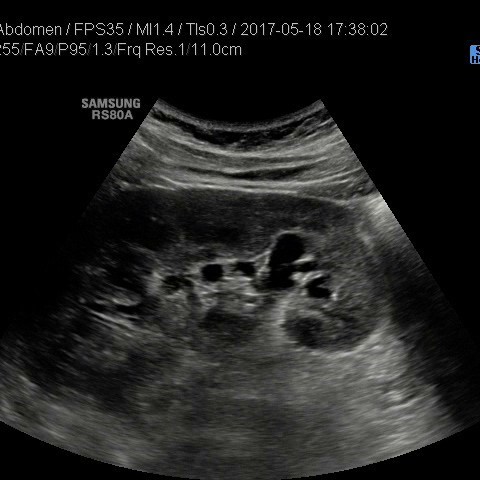

• USG jamy brzusznej

z oceną wątroby, trzustki, nerek, śledziony, pęcherza, gruczołu krokowego, dużych naczyń jamy brzusznej oraz przestrzeni okołoaortalnej.

• USG jamy brzusznej z oceną wątroby, trzustki, nerek, śledziony, pęcherza, gruczołu krokowego, dużych naczyń jamy brzusznej oraz przestrzeni okołoaortalnej